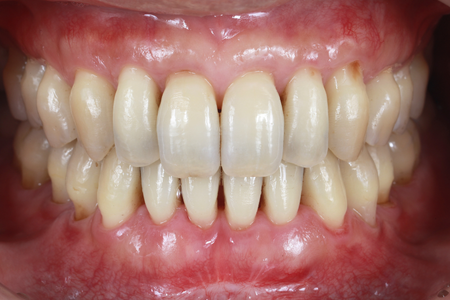

歯間の「黒い隙間」を修復|

40代 女性

歯間乳頭再建による審美性と機能性の回復

治療名 【高度審美形成】歯間乳頭再建術 治療期間 約1年 執刀医 Dr. 大杉 治療費 300,000円(税込) 治療解説 ブラックトライアングルに対し、歯を削ったり抜いたりせずに形態改善を目指して歯間乳頭再建術を行いました。

上顎口蓋から採取した結合組織を歯間部へ移植し、マイクロスコープ下で精密に縫合。

審美面の改善に加え、食渣(食べかす)が詰まりにくい状態の回復を目指しました。リスク・副作用 移植組織の定着後も、メンテナンスが予後を大きく左右します。

特に歯間ブラシの不適切な使用や過度なブラッシング圧は組織の退縮を招くため、術後は当院の指導に基づいた厳密なプラークコントロールが必要です。